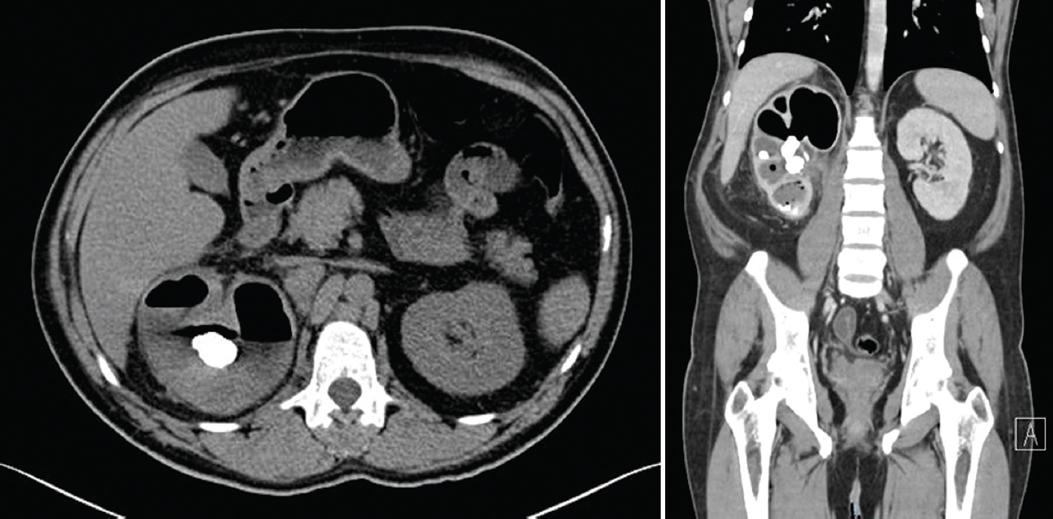

En las figuras 2 y 3 se ilustra un caso representativo de los 51 pacientes con PE, incluyendo hallazgos tomográficos.

Figura 2 Paciente de sexo masculino de 41 años con pielonefritis enfisematosa derecha Huang II y lito coral incompleto derecho, con reporte de urocultivo sin desarrollo. En la tomografía computada abdominopélvica se observa una imagen hiperdensa compatible con un lito piélico obstructivo de 900 UH, que condiciona dilatación de todo el sistema colector renal, más un lito a nivel del cáliz medio e inferior homolateral, además de gas en el parénquima y el sistema colector, con presencia de niveles hidroaéreos.